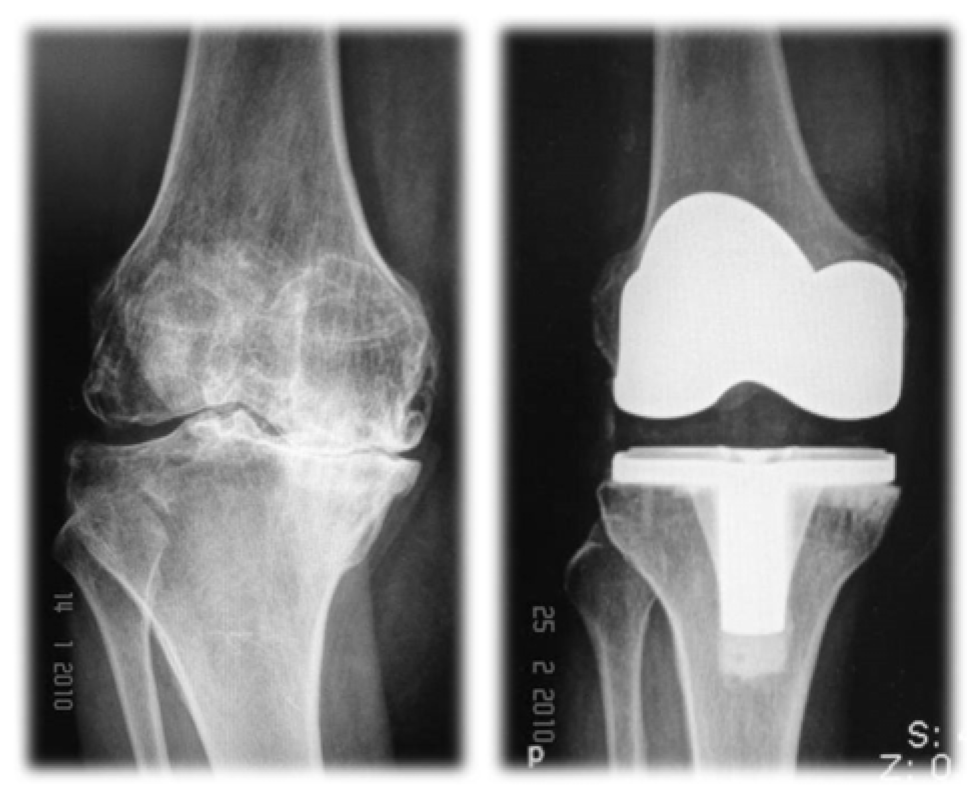

การผ่าตัดเปลี่ยนข้อเข่าเทียมคืออะไร

คือการผ่าตัดเพื่อนผิวข้อเข่าเดิมที่เสื่อมสภาพออก และทดแทนผิวข้อใหม่ด้วยข้อเข่า เทียม

ควรพิจารณาผ่าตัดเปลี่ยนข้อเข่าเทียมเมื่อใด

ผู้ป่วยโรคข้อเข่าเสื่อมที่รับการรักษาด้วยวิธีการไม่ผ่าตัด (การใช้ยา การทํากายภาพบําบัด และการปรับเปลี่ยนการใช้งานข้อเข่า) อย่างเต็มที่แล้วยังให้ผลการรักษาที่ไม่ดี โดยยังมีลักษณะ ต่อไปนี้อยู่

- ยังมีอาการปวดที่รุนแรงจนไม่สามารถทํากิจวัตรประจําวันพื้นฐานได้ปกติ เช่น ยืนเดิน ลําบาก ลุกนั่งลําบาก จําเป็นต้องใช้อุปกรณ์ช่วยพยุงเดินตลอด

- มีการผิดรูปของข้อเข่า เช่น เข่า โกงเข้าในหรือโก่งออกนอกอย่างมาก

- ข้อเข่ายึด พิสัยการเคลื่อนไหวข้อเข่าลดลง งอและเหยียดเข่าได้ไม่เต็มที่เหมือนเดิม

ผู้ป่วยจะหายจากอาการเจ็บปวด มีข้อเข่าที่ตรงและมั่นคง สามารถเดินและใช้งานได้ เหมือนหรือใกล้เคียงกับเข่าปกติโดยไม่ต้องใช้ยาอีก ผู้ป่วยมากกว่าร้อยละ 95 มีความพึงพอใจ ต่อการผ่าตัด